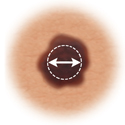

Diameter

If the mole's diameter is larger than a pencil's eraser